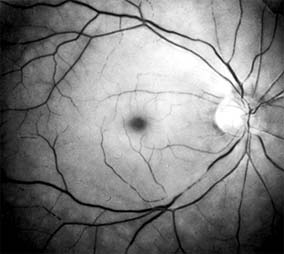

Chapter 10: Retina RETINAL VASCULAR DISEASES DIABETIC RETINOPATHY Diabetic retinopathy is one of the leading causes of blindness in the Western world. The view that chronic hyperglycemia of diabetes mellitus is the major determinant of diabetic retinopathy is supported by the observation that retinopathy in young people with type I (insulin-dependent) diabetes does not occur for at least 3-5 years after the onset of this systemic disease. Similar results have been obtained for type II (non-insulin-dependent) diabetes, but in such patients the time of onset and therefore the duration of disease are more difficult to determine precisely. It is recommended that patients with type I diabetes mellitus be referred for ophthalmologic examination within 3 years after diagnosis and reexamined on at least an annual basis. Type II diabetic patients should be referred for ophthalmologic examination at the time of diagnosis and reexamined at least annually. As diabetic retinopathy can become particularly aggressive during pregnancy, any diabetic woman who becomes pregnant should be examined by an ophthalmologist in the first trimester and at least every 3 months thereafter until parturition. In terms of both prognosis and treatment, it is useful to divide diabetic retinopathy into nonproliferative and proliferative categories. The prevalence of proliferative retinopathy in type I diabetics with 15 years of systemic disease is 50%. While the prevalence of proliferative disease at 15 years is much less in type II diabetics, the prevalence of macular edema as a function of the duration of systemic disease is the same in both groups. 1. NONPROLIFERATIVE DIABETIC RETINOPATHY Diabetic retinopathy is a progressive microangiopathy characterized by small vessel damage and occlusion. The earliest pathologic changes are thickening of the capillary endothelial basement membrane and reduction of the number of pericytes. Background diabetic retinopathy is a clinical reflection of the hyperpermeability and incompetence of involved vessels. The capillaries develop tiny dot-like outpouchings called microaneurysms, while the retinal veins become dilated and tortuous (Figure 10-20). Multiple hemorrhages may appear throughout different levels of the retina. Flame-shaped hemorrhages are so shaped because of their location within the horizontally oriented nerve fiber layer, while dot and blot hemorrhages are in the deeper retina, where cells and axons are vertically oriented. Macular edema is the most frequent cause of visual loss among patients with background diabetic retinopathy. The edema is caused primarily by a breakdown of the inner blood-retinal barrier at the level of the retinal capillary endothelium, allowing leakage of fluid and plasma constituents into the surrounding retina. The edema may be focal or diffuse and appears clinically as thickened, cloudy retina with associated microaneurysms and intraretinal exudate. Circinate zones of yellow, lipid-rich exudate may form around clusters of microaneurysms and are most frequently centered in the temporal portion of the macula. While the prevalence of macular edema is 10% in the diabetic population as a whole, there is a dramatic increase in prevalence in eyes with more severe retinopathy. With progressive microvascular occlusion, signs of increasing ischemia may be superimposed on the picture of background retinopathy and produce the clinical picture of preproliferative diabetic retinopathy. The most typical findings here are multiple cotton-wool spots, beading of the retinal veins, and irregular segmental dilation of the retinal capillary bed (intraretinal microvascular abnormalities). Closure of retinal capillaries surrounding the foveal avascular zone may cause significant ischemia, manifest clinically by the presence of large dark retinal hemorrhages and small thread-like macular arterioles. Eyes with macular edema and significant ischemia have a poorer visual prognosis-with or without laser treatment-than eyes with edema and relatively good perfusion. The visual and electrophysiologic dysfunctions associated with diabetes probably result from the local vascular abnormalities and the systemic metabolic effects of the disease to which the retina is subjected. A characteristic blue-yellow color vision abnormality develops, and hue discrimination may be impaired. Contrast sensitivity may be reduced in patients, even in the presence of normal visual acuity. Visual field testing may show relative scotomas corresponding to areas of retinal edema and nonperfusion, and abnormalities in dark adaptation have also been described. Electroretinographic abnormalities bear a relationship to the severity of retinopathy and may aid in predicting progression of retinopathy. Fluorescein angiography is invaluable in defining the microvascular abnormalities of diabetic retinopathy (Figures 10-21 and 10-22). Large filling defects of capillary beds-"capillary nonperfusion"-show the extent of retinal ischemia (Figure 10-23) and are usually most prominent in the midperiphery. The fluorescein leakage associated with retinal edema may assume the petaloid configuration of cystoid macular edema or may be diffuse. Other fluorescein abnormalities include vascular loops and intraretinal shunts. The focus of treatment in patients with nonproliferative diabetic retinopathy and no macular edema is treatment of hyperglycemia and intercurrent systemic disease. A controlled clinical trial has shown that aldose reductase inhibitor therapy does not prevent progression of diabetic retinopathy. Focal argon laser treatment of discrete points of retinal leakage in patients with clinically significant macular edema, principally defined as thickening of the retina at or within 500 2. PROLIFERATIVE DIABETIC RETINOPATHY The most severe ocular complications of diabetes mellitus are associated with proliferative diabetic retinopathy. Progressive retinal ischemia eventually stimulates the formation of delicate new vessels that leak serum proteins (and fluorescein) profusely. Neovascularization is frequently located on the surface of the disk and at the posterior edge of the peripheral zones of "nonperfusion" (Figures 10-24 and 10-25). Iris neovascularization, or rubeosis iridis, can also result. The fragile new vessels proliferate onto the posterior face of the vitreous and become elevated once the vitreous starts to contract away from the retina. If the vessels bleed (Figure 10-26), massive vitreous hemorrhage may cause sudden visual loss. Eyes in which posterior vitreous detachment is complete are at less risk of developing neovascularization and vitreous hemorrhage. In eyes with proliferative diabetic retinopathy and persistent vitreoretinal adhesions, elevated neovascular fronds may undergo fibrous change and form tight fibrovascular bands that tug on the retina and exert continued vitreous contraction. This can cause either a progressive traction retinal detachment or, if a retinal tear is produced, rhegmatogenous retinal detachment. The retinal detachment may be heralded or concealed by vitreous hemorrhage. When vitreous contraction is complete in these eyes, proliferative retinopathy tends to enter the burned-out or "involutional" stage. Treatment Argon laser panretinal photocoagulation is usually indicated in proliferative diabetic retinopathy. Patients at greatest risk of significant visual loss are those with preretinal or vitreous hemorrhage or neovascularization of the disk. Panretinal photocoagulation can significantly reduce the chance of massive vitreous hemorrhage and retinal detachment in these patients by causing the regression and, in some cases, the disappearance of new vessels. The technique involves scattering up to several thousand regularly spaced laser burns throughout the retina, sparing the central region bordered by the disk and the major temporal vascular arcades (Chapter 24). Although the mechanism is not precisely understood, panretinal photocoagulation presumably works by reducing the angiogenic stimulus from ischemic retina. The role of vitreoretinal surgery in proliferative diabetic eye disease continues to evolve. Conservative management of monocular vision impairing diabetic vitreous hemorrhage in the binocular patient had been to allow spontaneous resolution over the course of several months. The results of a 4-year study designed to assess the role of early vitrectomy for severe vitreous hemorrhage and proliferative diabetic retinopathy support this surgery as a means by which good vision may be restored or maintained. The role of vitreoretinal surgery in the treatment of diabetic traction retinal detachment is described elsewhere in this chapter. CENTRAL RETINAL ARTERY OCCLUSION The patient with central retinal artery occlusion routinely relates a history of painless catastrophic visual loss occurring over a period of seconds; antecedent transient visual loss (amaurosis fugax) may be reported. The visual acuity ranges between counting fingers and light perception in 90% of eyes at the time of initial examination. An afferent pupillary defect can appear within seconds after retinal arterial obstruction, preceding the fundus abnormalities by an hour. Ophthalmoscopically, the superficial retina becomes opacified except in the foveola, where a cherry-red spot is evident (Figure 10-27). The cherry-red spot is pigment of the choroid and retinal pigment epithelium viewed through the extremely thin overlying foveolar retina and contrasted with the thicker and translucent perifoveolar retina. Twenty-five percent of eyes with central retinal artery occlusion have cilioretinal arteries that spare macular retina and may preserve some central visual acuity. Clinically, the retinal opacification resolves within 4-6 weeks, leaving a pale optic disk as the major ocular finding. In older patients, giant cell arteritis must be excluded and if necessary treated immediately with high doses of systemic corticosteroids. Other causes of central retinal artery occlusion are arteriosclerosis and emboli from carotid or cardiac sources. These are discussed further in Chapter 15. Treatment Because irreversible retinal damage has been shown to occur after 90 minutes of complete central retinal artery occlusion in the subhuman primate model, precious little time is available in which to begin therapy. Anterior chamber paracentesis can be employed in order to decrease intraocular pressure and increase retinal perfusion. This is particularly indicated in embolic central retinal artery occlusion. Intravenous acetazolamide has been used to decrease intraocular pressure, and an inhaled oxygen-carbon dioxide mixture has been employed to induce retinal vasodilation and increase the PO2 at the retinal surface. Direct infusion of a thrombolytic agent into the ophthalmic artery can result in recovery of vision. It must be performed within 8 hours after onset of the central retinal artery occlusion, requires specific radiologic expertise, and there is a risk of cerebral infarction. Systemic anticoagulants are generally not employed. BRANCH RETINAL ARTERY OCCLUSION Branch retinal artery occlusion usually presents with sudden loss of visual field and with reduction in visual acuity if the fovea is involved. Fundus signs of retinal edema with associated cotton-wool spots are limited to the area of retina supplied by the occluded vessel. Embolic causes are proportionately more common than in central retinal artery occlusion, and emboli are frequently identified on clinical examination (see Chapter 15). Migraine, oral contraceptive use, and vasculitis must also be considered. CENTRAL RETINAL VEIN OCCLUSION Central retinal vein occlusion is a common and easily diagnosed retinal vascular disorder with potentially blinding complications. The patient presents with sudden painless loss of vision. The clinical appearance varies from a few small scattered retinal hemorrhages and cotton-wool spots (Figure 10-28) to a marked hemorrhagic appearance with both deep and superficial retinal hemorrhage, which may rarely break through into the vitreous cavity. Most patients who develop the disease are over 50 years of age, and more than half have associated cardiovascular disease. Predisposing factors and their investigation are discussed in Chapter 15. Chronic open-angle glaucoma should always be excluded (see Chapter 11). The two major complications associated with central retinal vein occlusion are reduced vision from macular edema and neovascular glaucoma secondary to iris neovascularization. Macular dysfunction occurs in almost all eyes with central vein occlusion. Although some eyes will show spontaneous improvement, most eyes will have persistent decreased central vision as a result of chronic macular edema. Nearly one-third of eyes with central retinal vein occlusion show significant retinal capillary nonperfusion on fluorescein angiography; one-half of these eyes will develop neovascular glaucoma. Treatment Careful follow-up evaluation is warranted, and prompt panretinal laser photocoagulation is recommended for eyes that develop anterior segment neovascularization. No treatment for macular edema, including grid pattern photocoagulation, has proved effective to date. BRANCH RETINAL VEIN OCCLUSION Branch retinal vein occlusion presents as sudden unilateral vision loss with segmentally distributed intraretinal hemorrhage. The vein occlusion always occurs at the site of an arteriovenous crossing (Figure 10-29), and retinal neovascularization may develop if the occlusion produces an area of retinal capillary nonperfusion that is more than 5 disk diameters in area. Sight-threatening complications of the disease are macular edema, macular ischemia, and vitreous hemorrhage from retinal neovascularization. Treatment Once peripheral retinal neovascularization has developed, sectoral laser retinal photocoagulation to the area of ischemic retina reduces the risk of vitreous hemorrhage by one-half. When vision loss due to macular edema persists for several months without spontaneous improvement, grid pattern argon laser macular photocoagulation may be indicated. Anticoagulant therapy has not been shown to be beneficial in either the prevention or the management of branch retinal vein occlusion. Investigation for an underlying systemic cause is discussed in Chapter 15. Important associated ocular diseases are chronic open-angle glaucoma and uveitis secondary to Behçet's syndrome. RETINAL ARTERIAL MACROANEURYSM Retinal macroaneurysms are fusiform or round dilations of the retinal arterioles occurring within the first three orders of arteriolar bifurcation. Most cases are unilateral, and the superotemporal artery is the most commonly involved vessel. Two-thirds of patients have associated systemic arterial hypertension. The most common clinical symptom is loss of central vision as a result of retinal edema, exudation, or hemorrhage. Macroaneurysms may bleed into the subretinal space, into the retina, beneath the internal limiting membrane, or into the vitreous; the "hourglass" hemorrhage is typical and is due to bleeding beneath and anterior to the retina. Although no clear indication for treatment with laser photocoagulation has been established, laser treatment of the macroaneurysm should be considered if lipid exudate coming from it threatens the fovea. PREVIOUS | NEXT Page: 1 | 2 | 3 | 4 | 5 | 6 | 7 | 8 | 9 10.1036/1535-8860.ch10 |